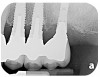

Fig 2. Radiograph suggested moderate bone loss around the implants.

Figure 2